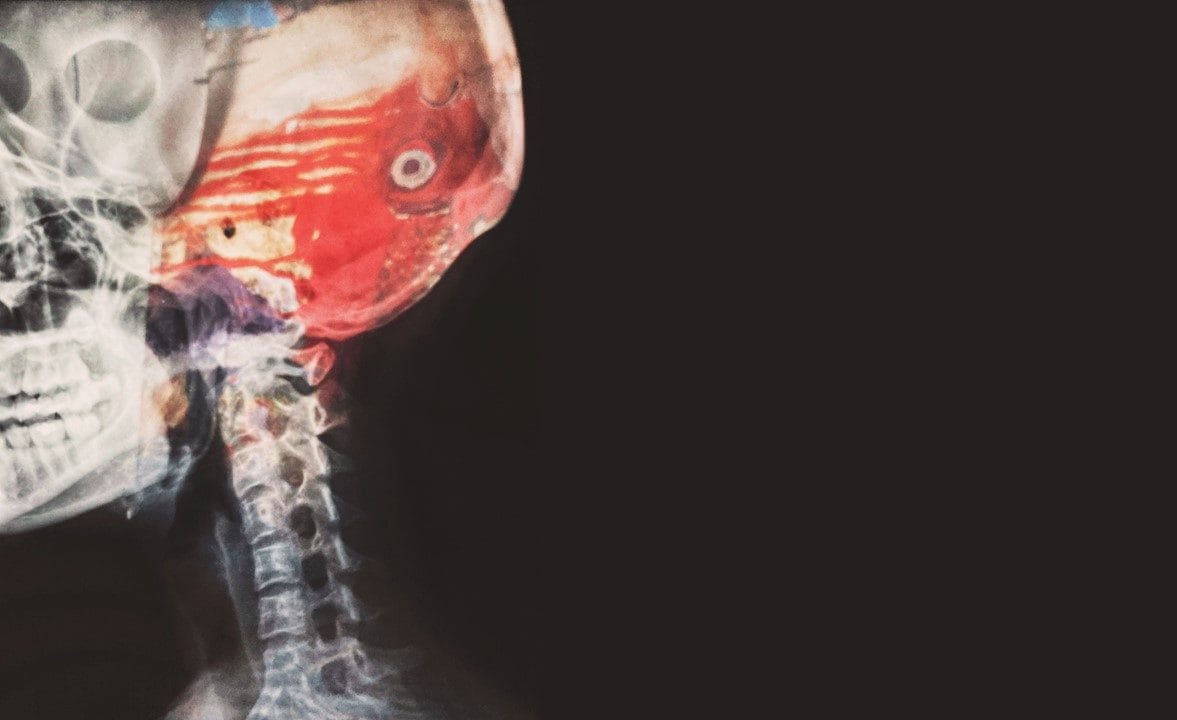

腦血管主要的疾病分為「腦缺血(cerebral ischemia)」和「腦出血(cerebral hemorrhage)」 二種。這二者都是腦部正常的血液循還被破壞,造成腦部的氧氣和能量供應不足,使得腦細胞無法正常新陳代謝。

腦組織缺氧就會壞死,腦功能也會逐漸隨之喪失。患者會在症狀上呈現意識和運動的嚴重停滯或障礙,也就是一般所稱的「腦中風(Stroke)」。 中風是因為通往大腦的血流受到干擾,導致大腦組織和功能受損。 中風後的復健和治療,也因損害的腦區不同而有差異。